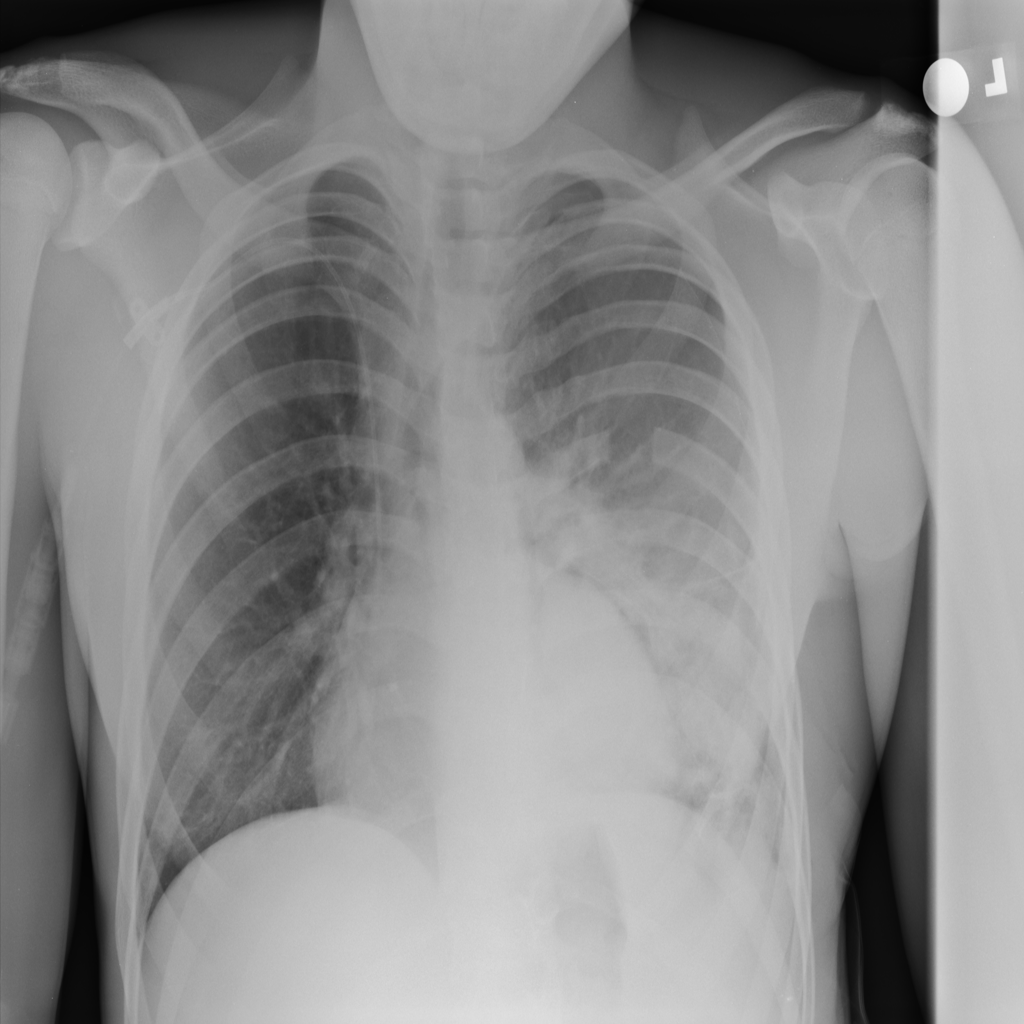

PAT-4639 · IMG-012Pneumothorax

PAT-4639 · IMG-012

AP